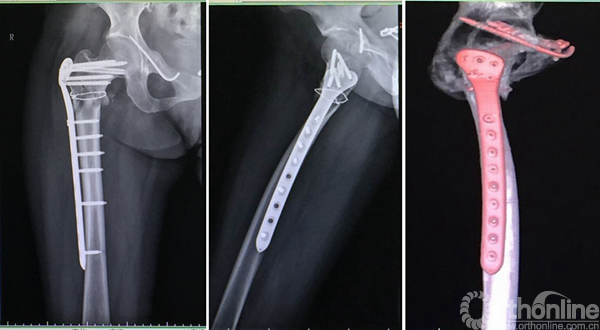

进针点和力线很难把握,即使应用很巧妙的复位技术获得了术后很好的力线,避免了髋内翻,但如此大块的骨块劈裂游离不处理,会存在退钉和骨不连或者髓内钉断裂的风险。

钱XX,女,43岁

术后